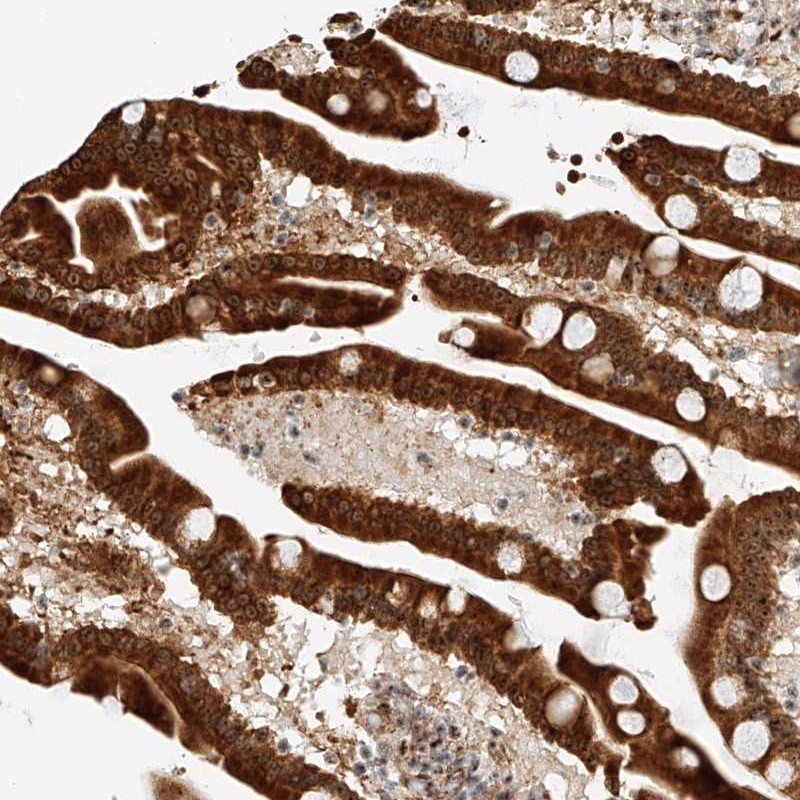

Immunohistochemical staining of human duodenum shows cytoplasmic and nuclear positivity in glandular cells.